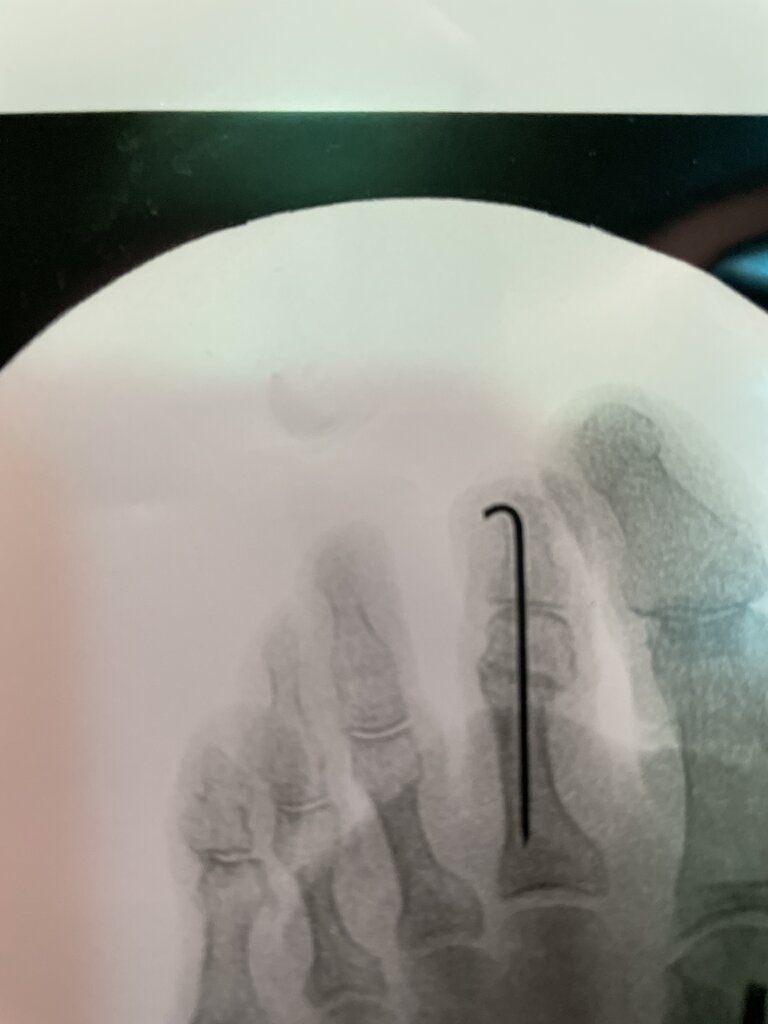

Arthrex DynaNite® FlexWire and DynaNite PIP Implant for Hammertoe Hcpcs Code For Hammertoe Implant What is the most appropriate way(s) to bill for the correction of a hammertoe deformity? Codes requiring a 7th character are represented by +: 28108 excision or curettage of bone cyst or benign. No additional payment will be provided. Prosthetic implant, no otherwise specified this code reports prosthetic implants that are not otherwise described in more specific hcpcs level ii. Hcpcs Code For Hammertoe Implant.

Hammertoe Correction Using the DynaNite® PIP Hammertoe Implant YouTube Hcpcs Code For Hammertoe Implant Prosthetic implant, no otherwise specified this code reports prosthetic implants that are not otherwise described in more specific hcpcs level ii codes. No additional payment will be provided. What is the most appropriate way(s) to bill for the correction of a hammertoe deformity? Hammertoe correction of the pip joint or mallet toe correction of the dip joint commonly involves arthrodesis. Hcpcs Code For Hammertoe Implant.

Arthrex DynaNite® PIP Hammertoe Implant Hcpcs Code For Hammertoe Implant Codes requiring a 7th character are represented by +: What is the most appropriate way(s) to bill for the correction of a hammertoe deformity? Prosthetic implant, no otherwise specified this code reports prosthetic implants that are not otherwise described in more specific hcpcs level ii codes. No additional payment will be provided. No additional payment will be provided. Hammertoe correction. Hcpcs Code For Hammertoe Implant.